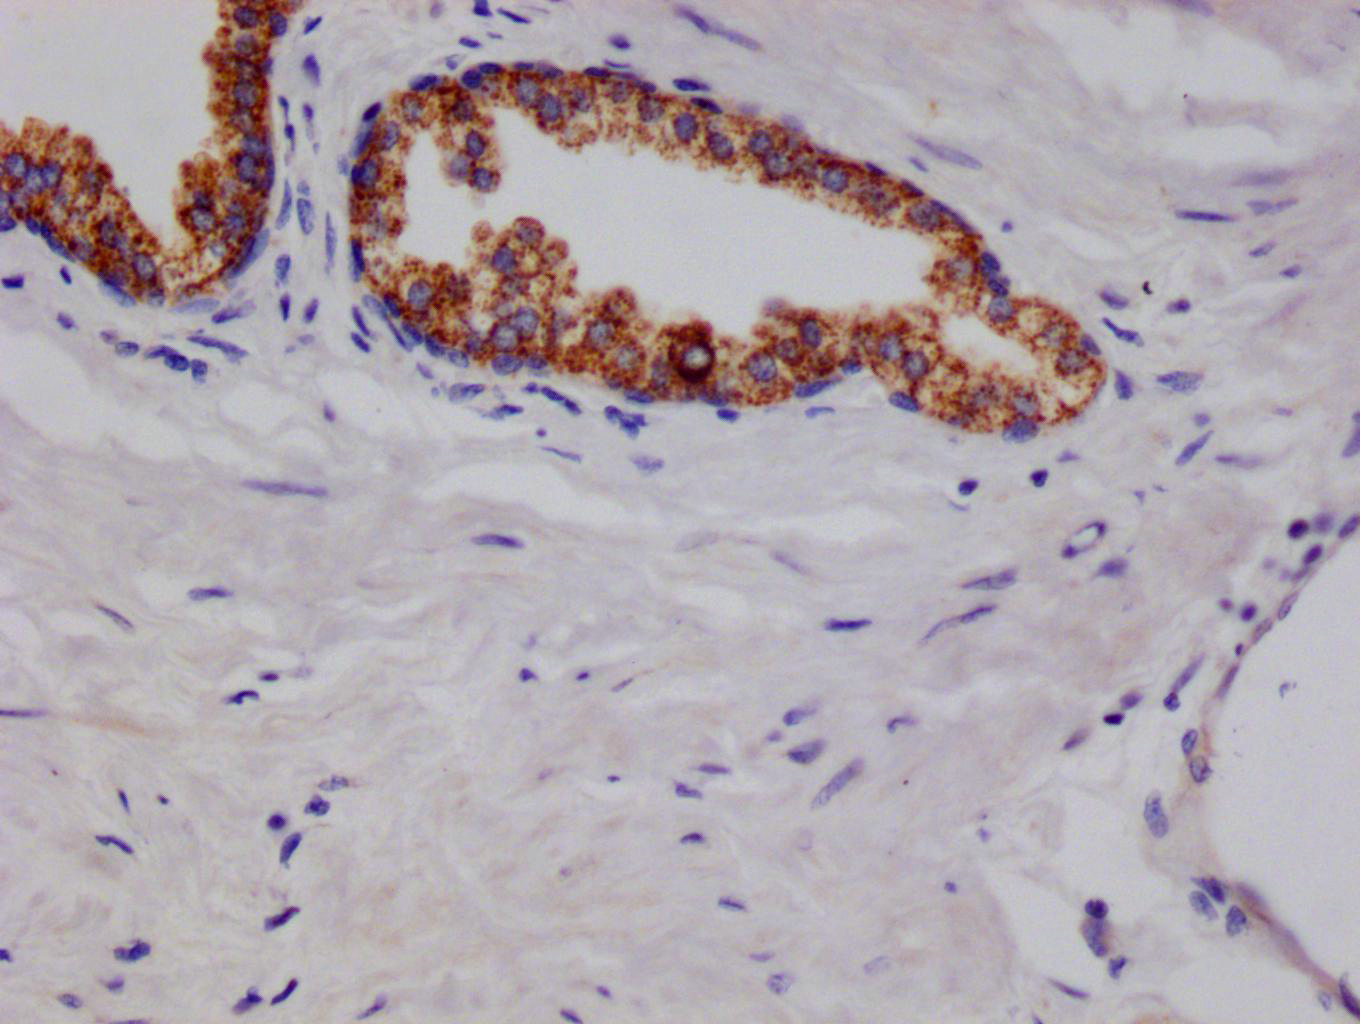

IHC image of CSB-RA216908A0HU diluted at 1:100 and staining in paraffin-embedded human prostate cancer performed on a Leica BondTM system. After dewaxing and hydration, antigen retrieval was mediated by high pressure in a citrate buffer (pH 6.0). Section was blocked with 10% normal goat serum 30min at RT. Then primary antibody (1% BSA) was incubated at 4°C overnight. The primary is detected by a Goat anti-rabbit polymer IgG labeled by HRP and visualized using 0.05% DAB.